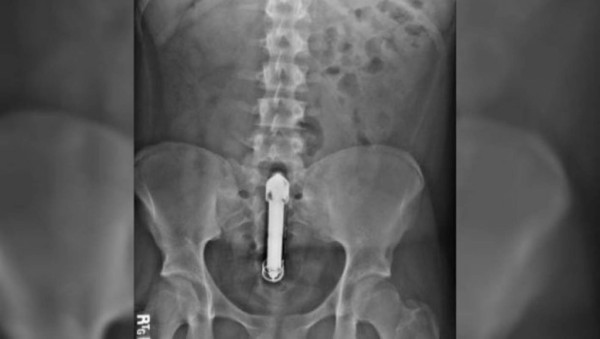

Los médicos revelaron que el vibrador había perforado su intestino.

Los médicos revelaron que el vibrador había perforado su intestino, lo que lo llevó a un fallo multiorgánico, sepsis y una perforación en el intestino.